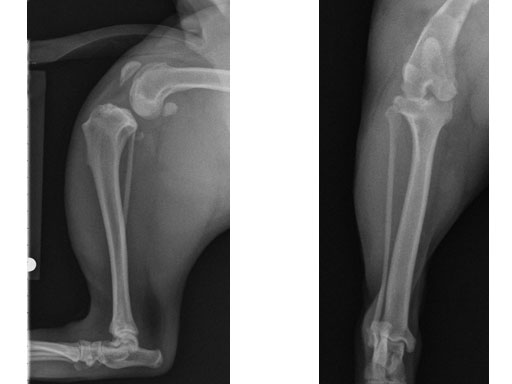

Case 3: Eight-year-old Australian cattle dog

(Case provided by Brian Beale, Houston, USA)

An 8-year-old, female, spayed, 24 kg Australian cattle dog. This breed has short stocky legs and is very energetic and strong. The added strength of the 3.5 mm plate over the TPLO 2.7 mm plate was an advantage. The smaller head profile and shorter length of the TPLO 3.5 mm small stature plate allowed it to fit nicely on this patient.